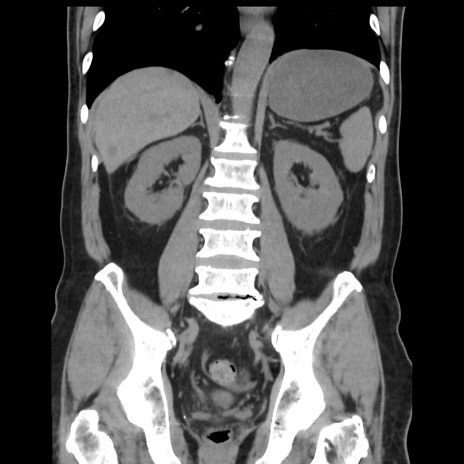

症例16(冠状断像)

【現病歴】 約1ヶ月前より間欠的に腹痛と嘔吐あり、当院消化器内科を受診したところCTで多発する肝臓のLDAを指摘され、精査中であった。以降は消化器症状は安定していたが、2日前より嘔気と腹痛があり、同日より排便・排ガスが消失した。改善認めず、 本日、救急外来を受診した。

【データ】WBC 7200、CRP 0.77